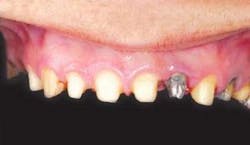

The Wol-Ceram® system represents a true breakthrough in the field of esthetic all-ceramic restorations. Wol-Ceram (figs. 1 & 2) is the first all-ceramic system that allows you to prepare teeth with a feather-edge margin — shoulders and chamfers are not required. Many dentists have complained about the extra preparation required for most all-ceramic restorations, feeling that a standard PFM preparation should be an adequate reduction. Because Wol-Ceram utilizes an electro-deposition dipping technique, it can handle any margin you prepare, even if there is a shoulder, chamfer, and feather-edge margin all on the same tooth (fig. 3).

Since the Wol-Ceram coping is shaded to match the final shade of the restoration, it is more forgiving in cases where the doctor has provided minimally acceptable reduction. While Wol-Ceram allows you to prepare more conservative margins than other all-ceramics, it still requires a 1.5 mm reduction, similar to that of a PFM crown (figs. 9-21).